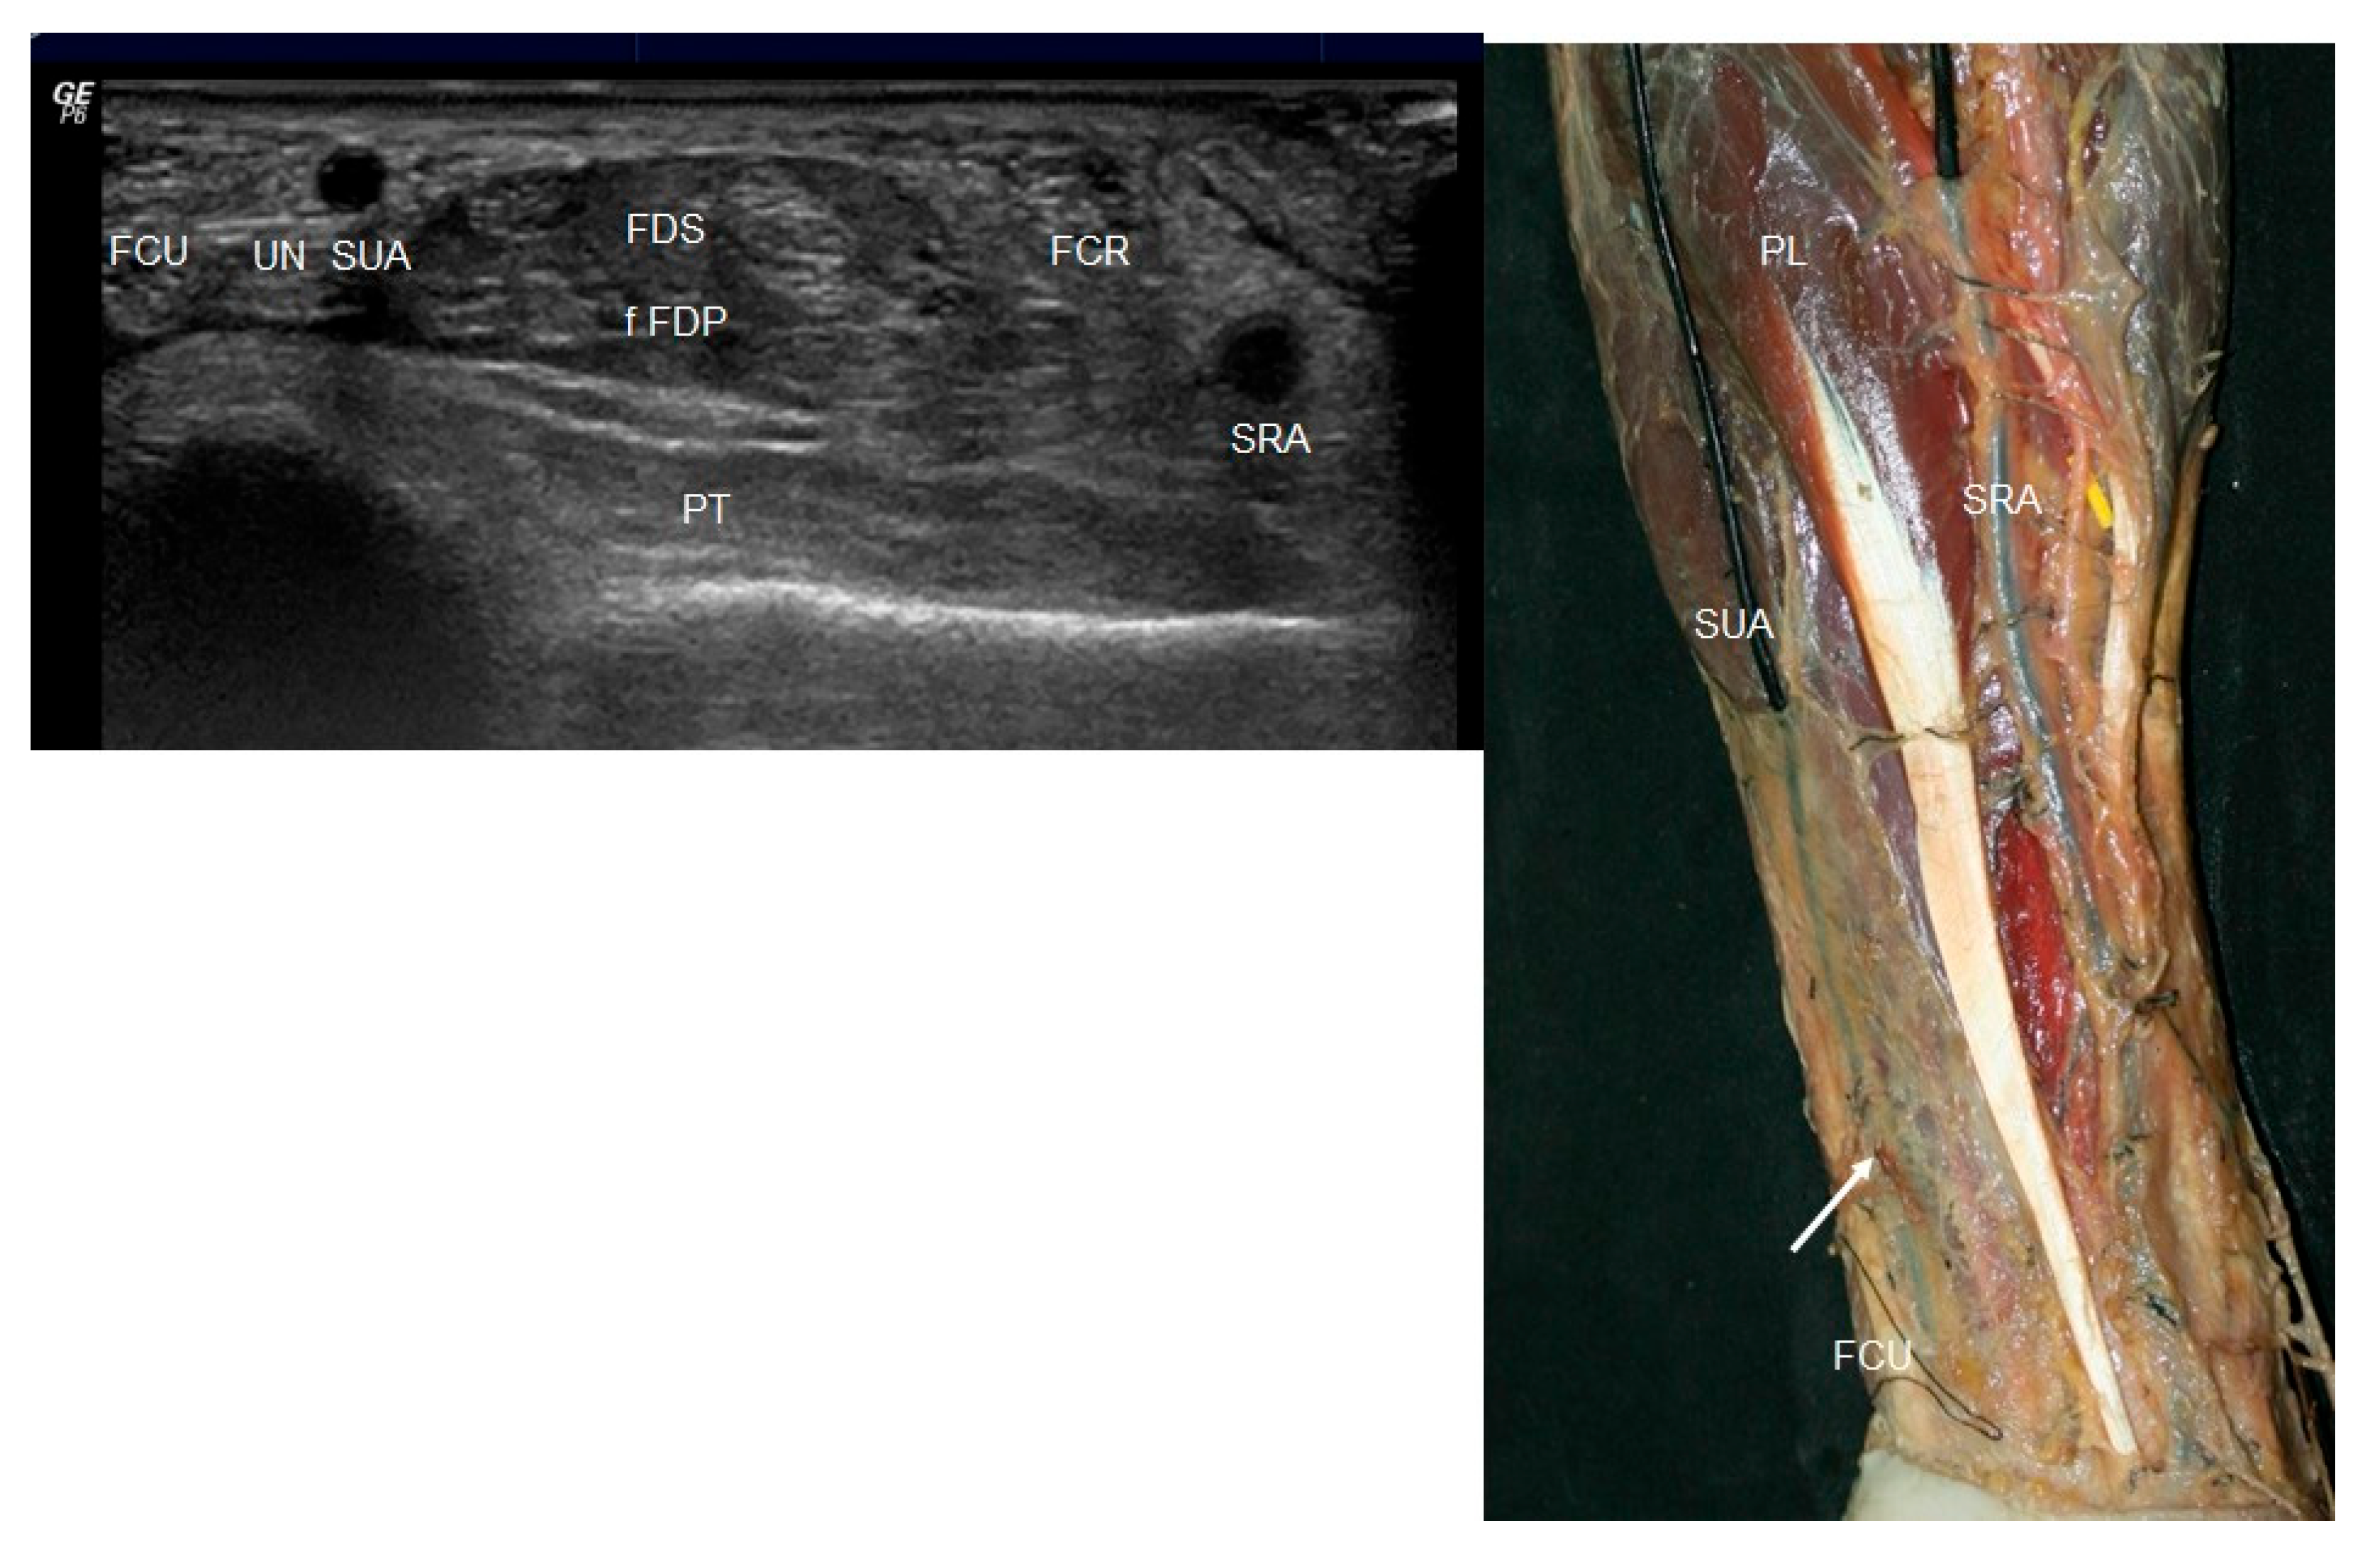

3.1. Ultrasound Study

3.2. Anatomical Study